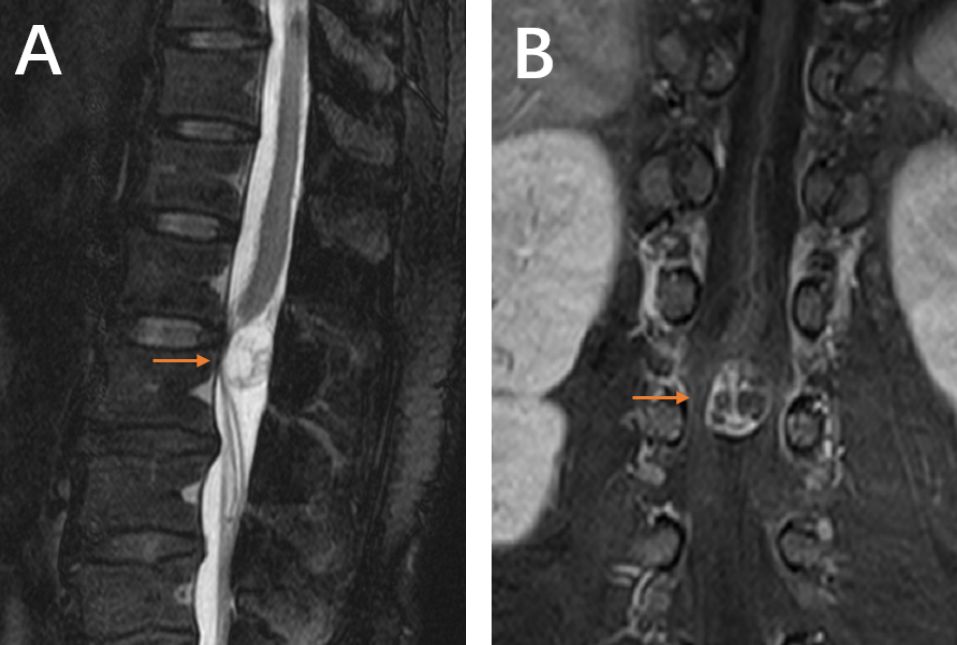

患者术后疼痛缓解,第2天下床活动。术后5天复查腰MRI(图4)未见肿瘤残留,左侧椎旁肌肉无明显损伤。术后病理(图5)提示(L1-2椎管内)神经鞘瘤。

图5. 病理结果:L1-2椎管内神经鞘瘤。